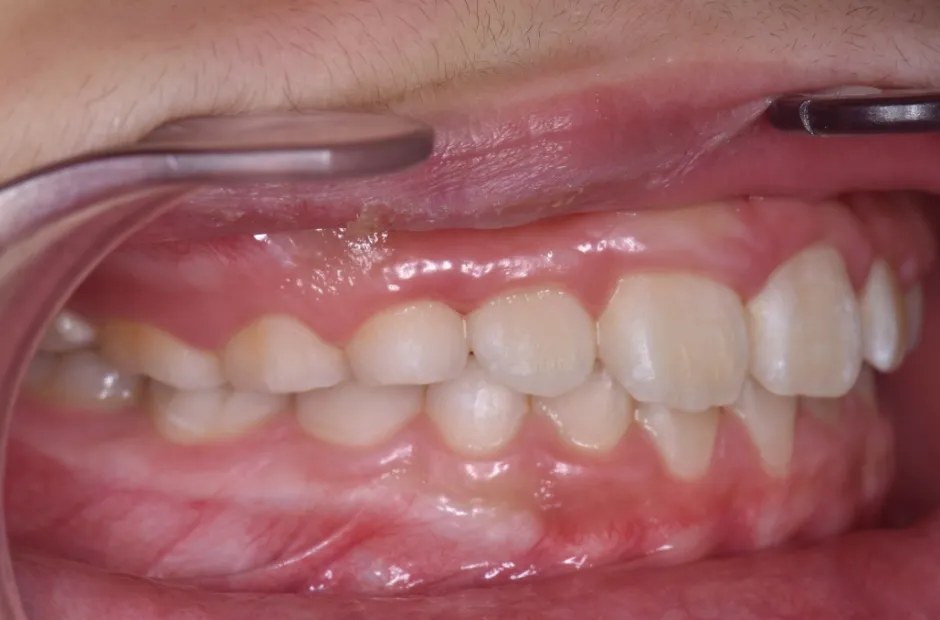

治療症例

ブラケット矯正

前歯部反対咬合

| 診断名・主訴 | 前歯部反対咬合 |

|---|---|

| 年齢・性別 | 14歳・男性 |

| 治療期間・回数 | 1年2か月 |

| 治療に用いた主な装置 | ブラケット矯正 |

| 抜歯部位 | なし |

| 治療費 | 60万円(税抜) |

| リスク・副作用 | 装置による違和感・疼痛・歯肉退縮・歯根吸収・虫歯のリスクなど |

治療前